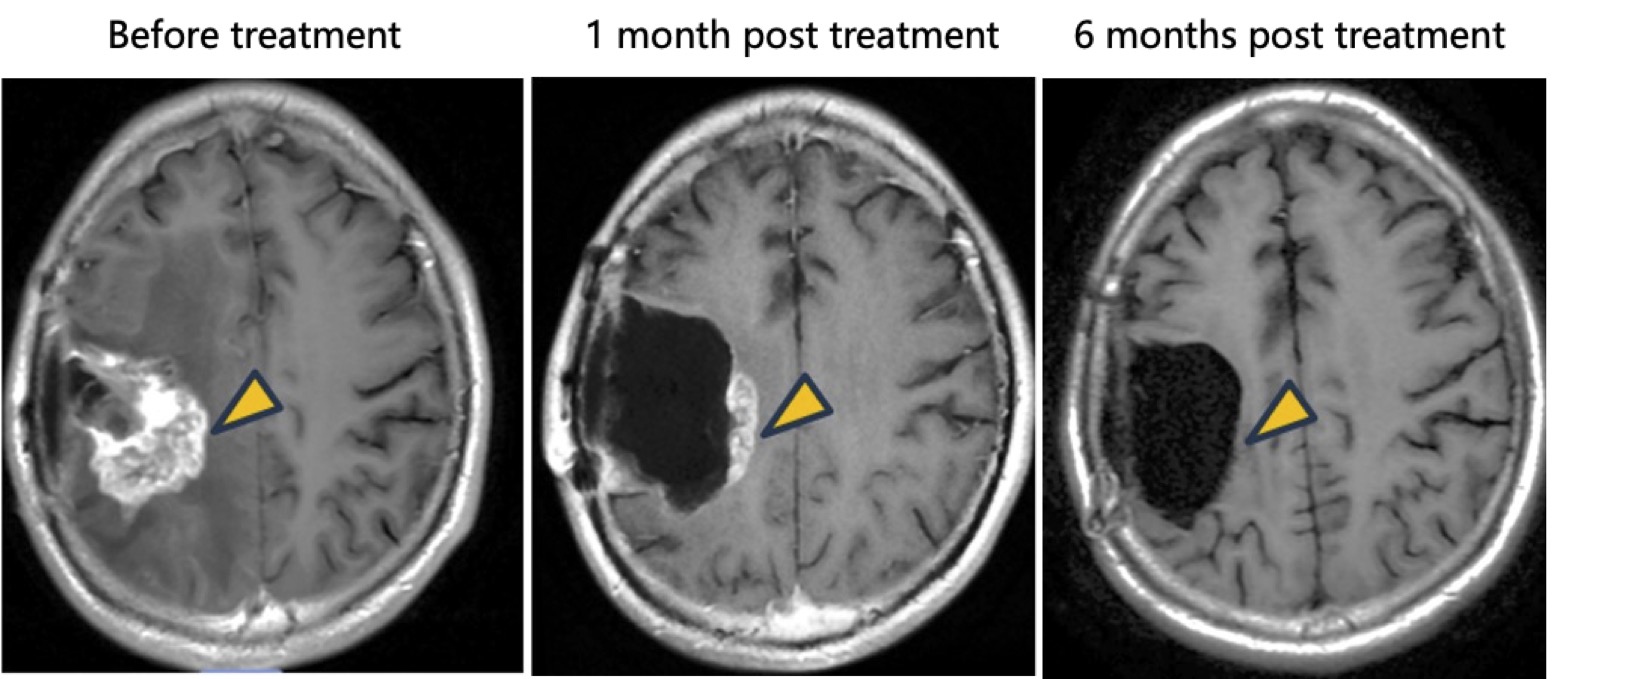

- Tumor Response: The patient receiving intratumoral injection demonstrated a clear therapeutic effect, with significant regression of target lesion.